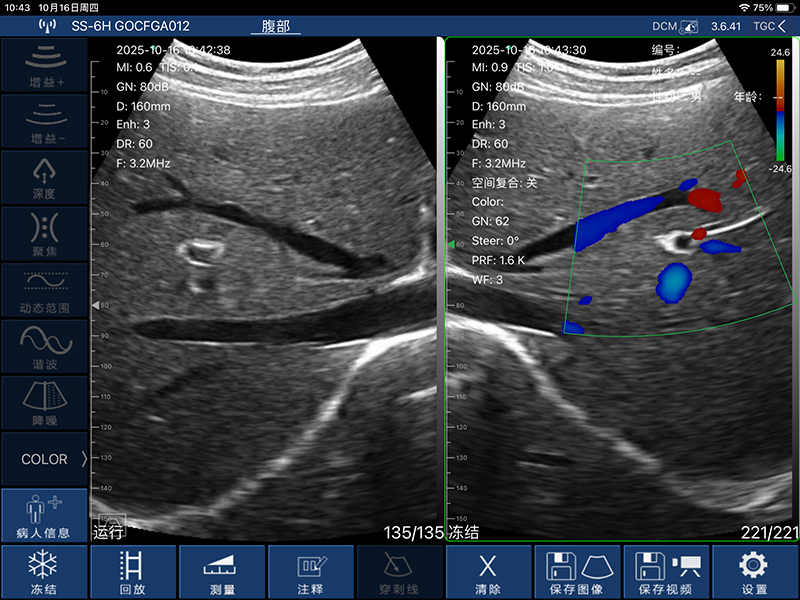

• 显示模式:B、B/M、Color、PW、PDI

• 穿刺辅助功能:平面内穿刺引导线功能,平面外穿刺引导与血管自动测量功能